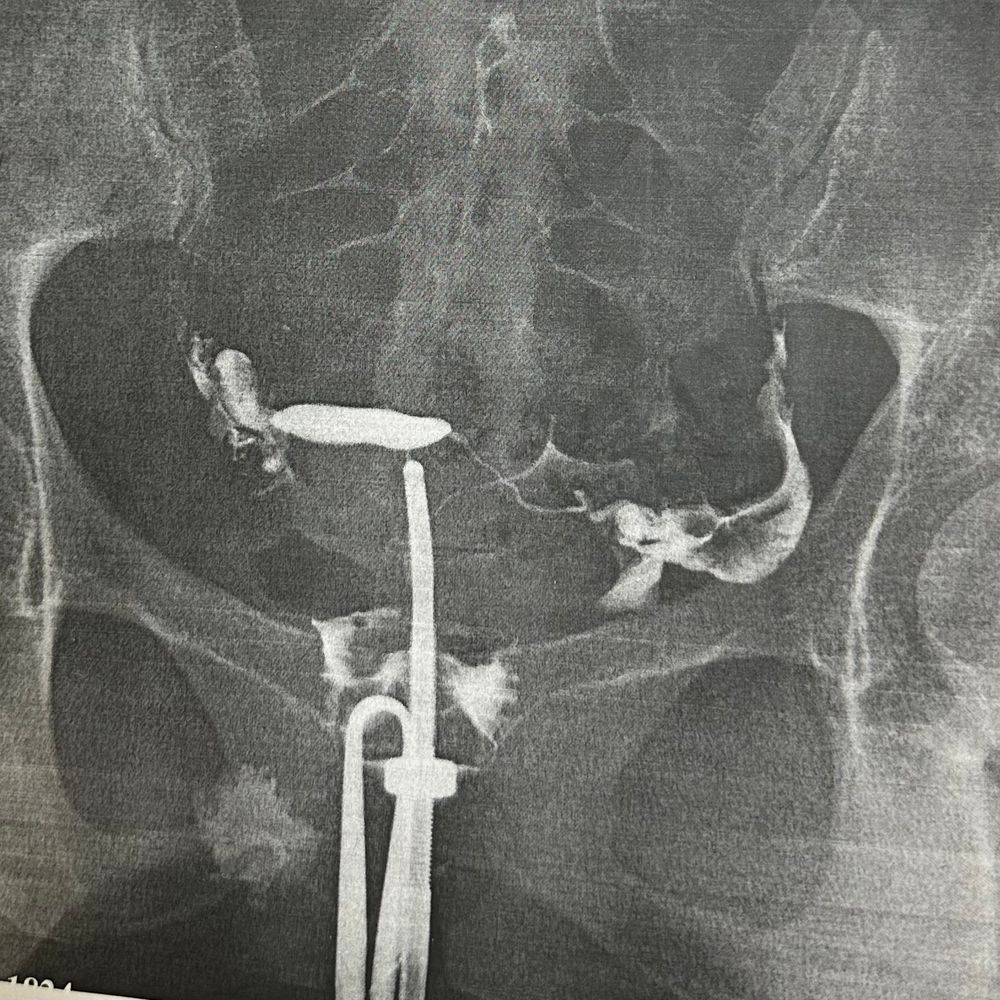

в итоге, ВСЕ ТРУБЫ ПРОХОДИМЫ!!! Ура! Но из-за этого, получается, у нас мужской фактор скорее всего проблема, потому что у меня, вроде ВСЕ В НОРМЕ! Как новенькая все врачи говорят.